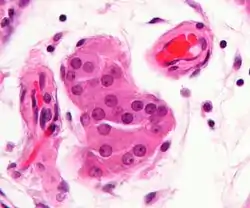

Micrograph showing a cluster of Leydig cells (center of image). H&E stain. | |

Leydig cells, also known as interstitial cells of the testes and interstitial cells of Leydig, are found adjacent to the seminiferous tubules in the testicle and produce testosterone in the presence of luteinizing hormone (LH).[1][2] They are polyhedral in shape and have a large, prominent nucleus, an eosinophilic cytoplasm, and numerous lipid-filled vesicles.[3]

The mammalian Leydig cell is a polyhedral epithelioid cell with a single eccentrically located ovoid nucleus. The nucleus contains one to three prominent nucleoli and large amounts of dark-staining peripheral heterochromatin. The acidophilic cytoplasm usually contains numerous membrane-bound lipid droplets and large amounts of smooth endoplasmic reticulum (SER).[4] Besides the abundance of SER with scattered patches of rough endoplasmic reticulum, several mitochondria are also prominent within the cytoplasm. Reinke crystals have lipofuscin pigment and rod-shaped crystal-like structures 3 to 20 micrometres in diameter.[5]